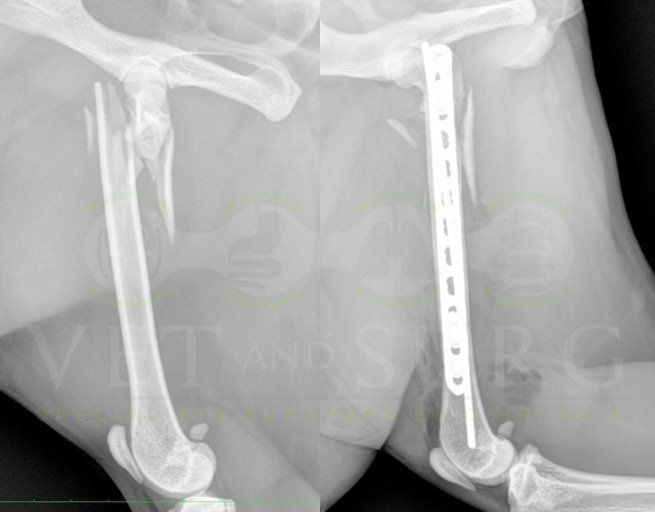

Fracture Salter-Harris sur un chaton Européen de 10 mois

Spike, chaton européen mâle de 10 mois, a été présenté en consultation pour boiterie du membre postérieur droit à la suite d'une chute depuis le 1er étage.

A la radiographie, une fracture de type Salter-harris 1 est diagnostiquée, avec déplacement de l'about discal.

Une réduction de la fracture par pose de 2 broches en croix a été réalisée.